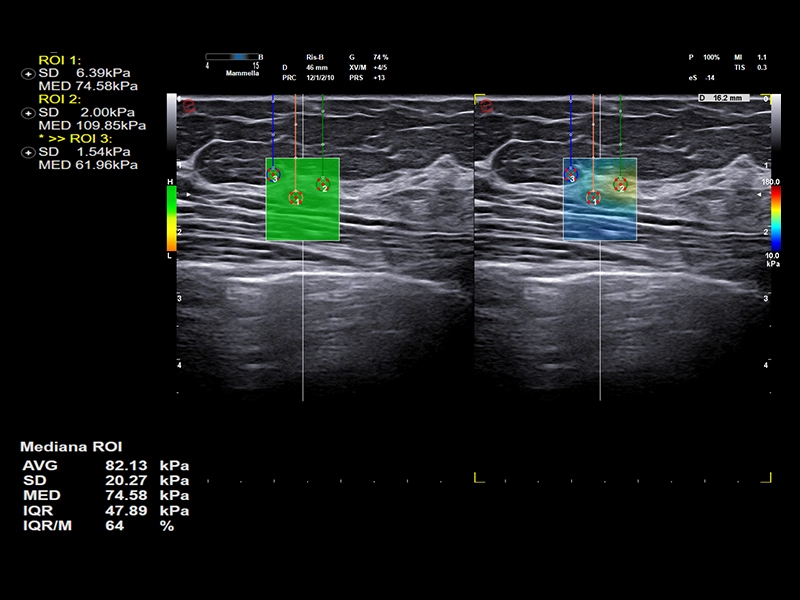

MyLab™C30 - SWE breast

MyLab™C30 - SWE breast

MyLab™C25 - ElaXto in breast

MyLab™C25 - ElaXto in breast

MyLab™9 Platform - Dual ElaXto characterization on breast lesion

MyLab™9 Platform - Dual ElaXto characterization on breast lesion

MyLab™9 Platform - Elastography advanced measurement package on breast lesion

MyLab™9 Platform - Elastography advanced measurement package on breast lesion